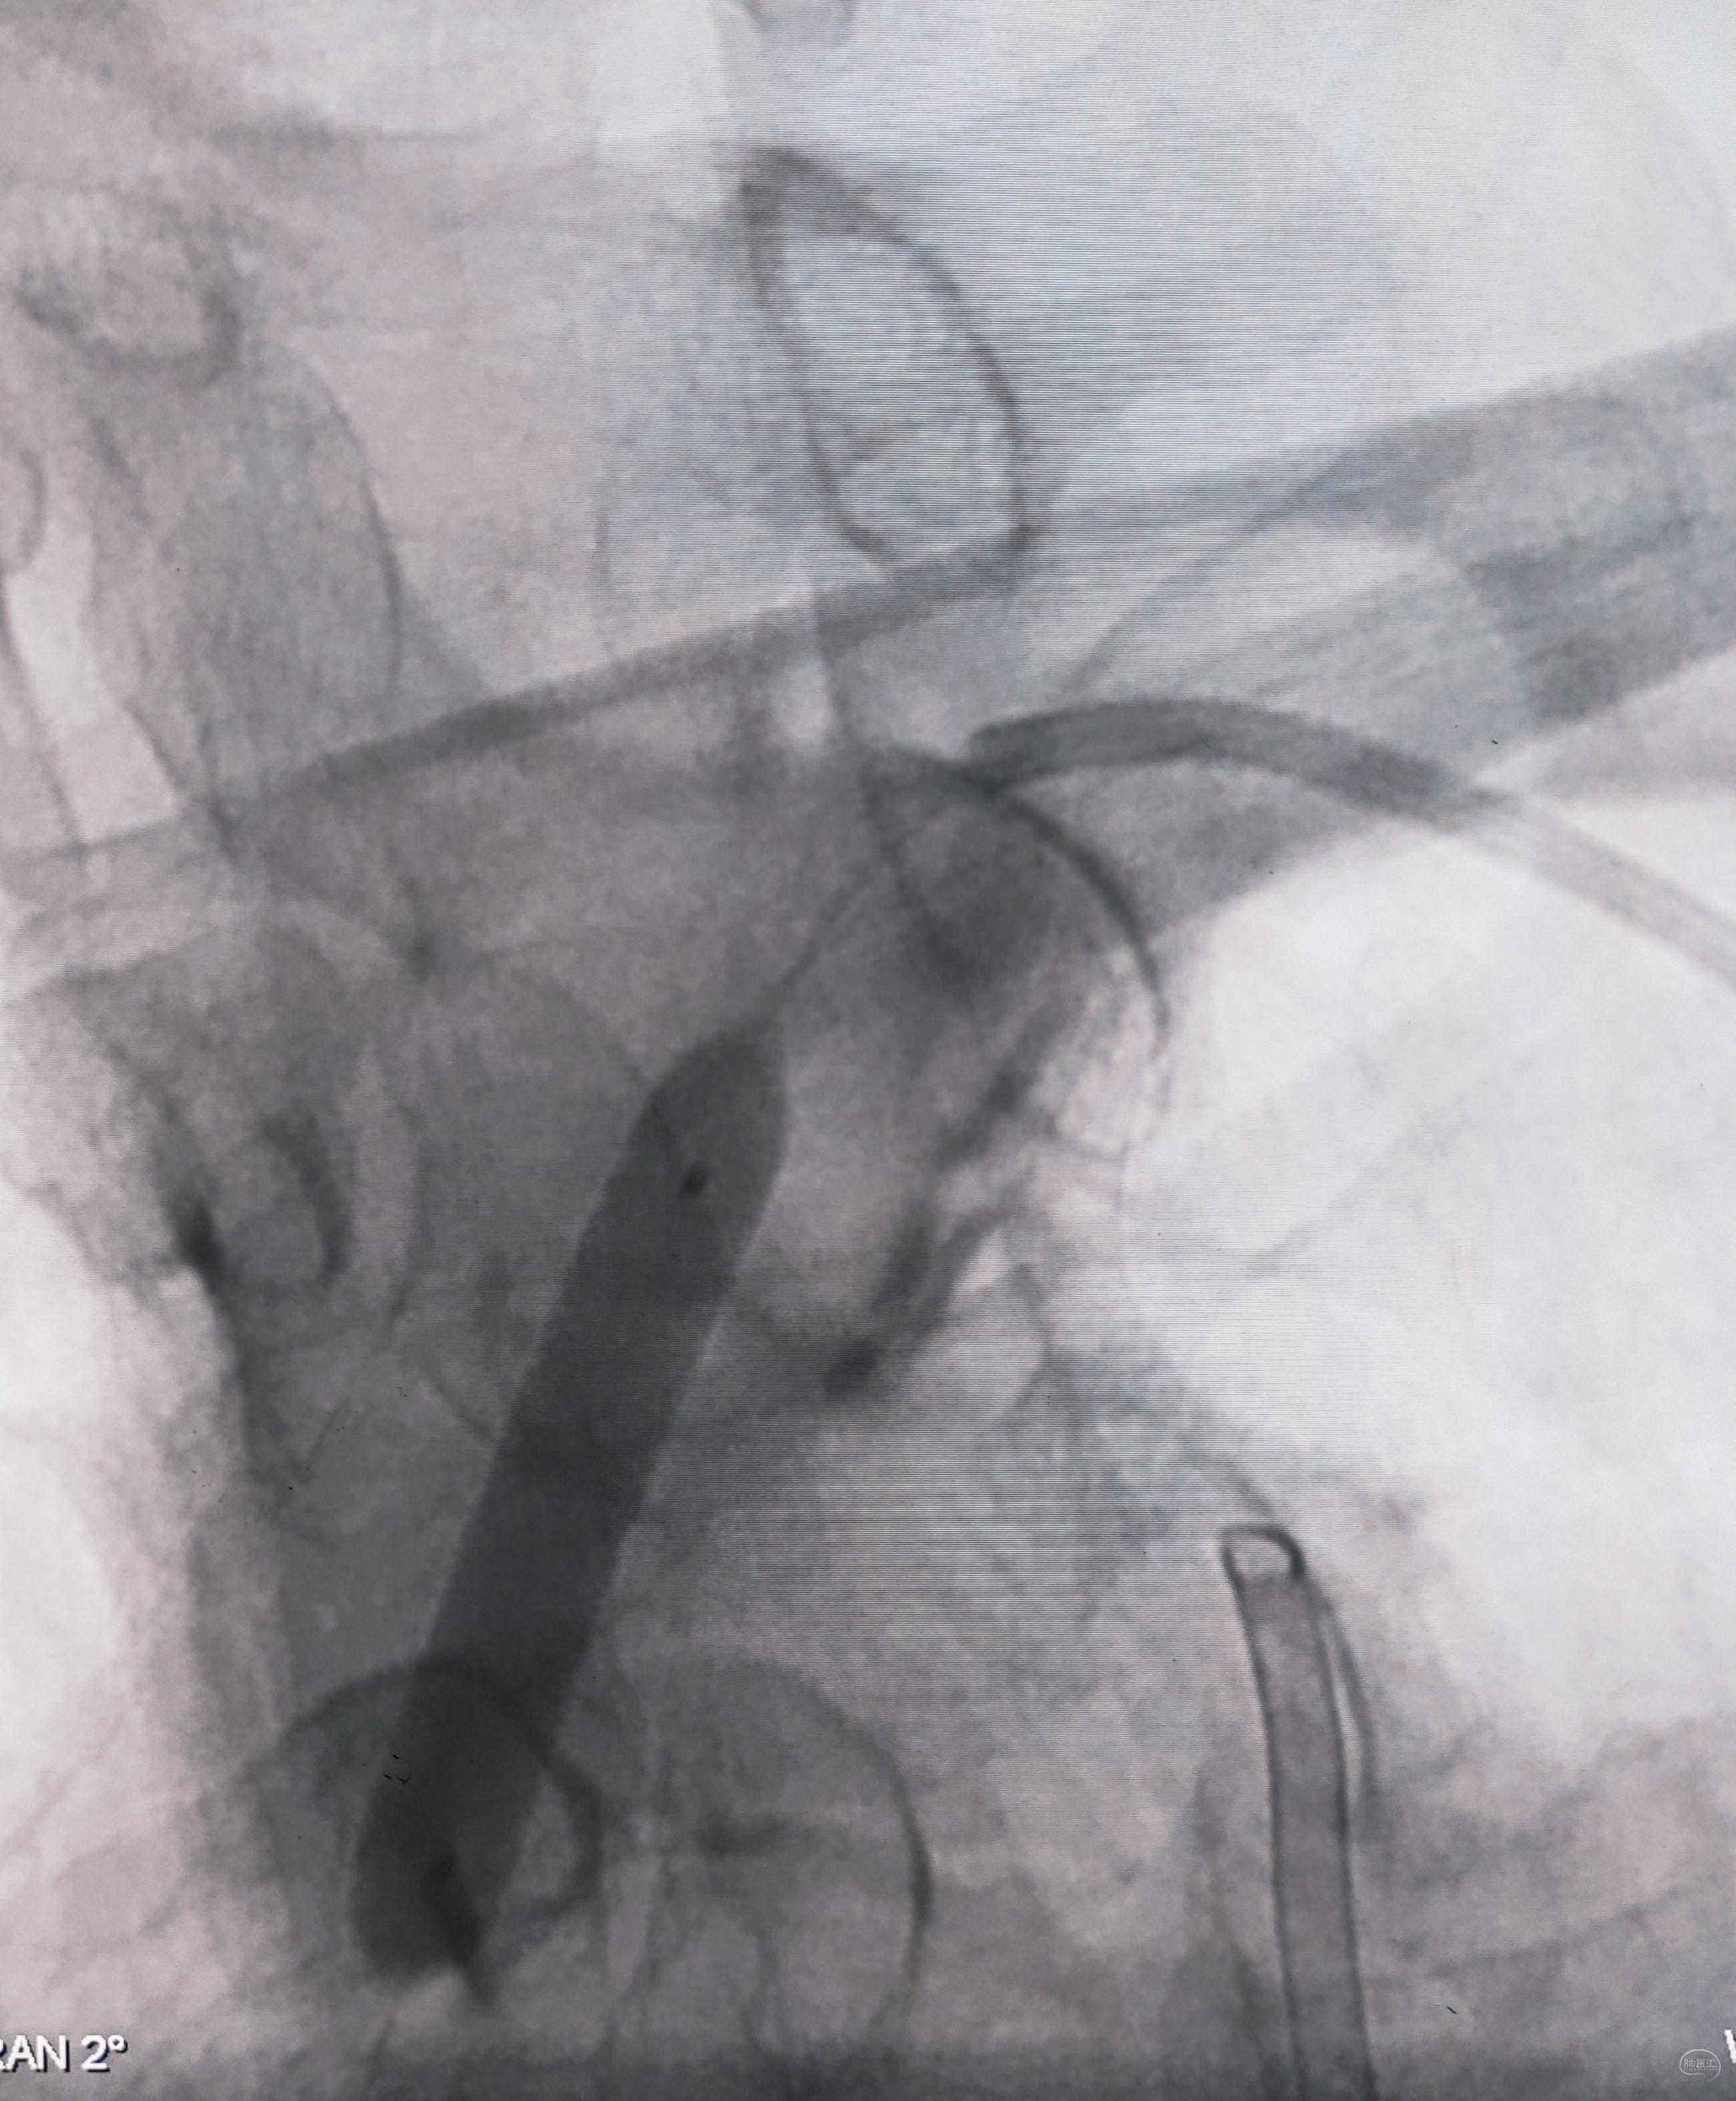

右侧锁骨下造影:右侧椎动脉开口也是重度狭窄,血流速度缓慢,闸门效应明显,此刻,不禁感叹血管的伟大,自己都狭窄得不要不要的了,还努力给对侧代偿供血,奉献精神佳!

右侧颈总动脉正侧位造影:意料之外的是,枕动脉通过肌支与右侧椎动脉吻合(紫色箭头),像极了《大风吹》的歌词“借一杯天上的水”,源源不断进行着血流的补充。但是好景不长,同侧V4段明显狭窄,无情的设置了第二道坎(绿色箭头)。